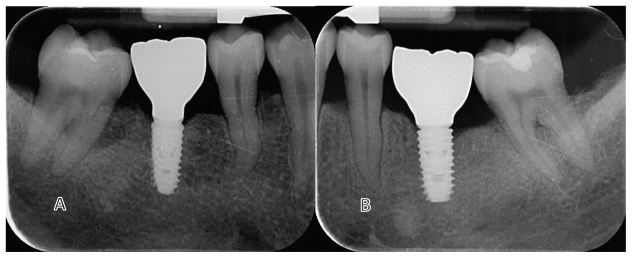

All surgeries were performed under local anesthesia with articaine hydrochloride and adrenaline 1:100,000 (Orabloc, Pierrel, Milan, Italy). After crestal incision and full-thickness flap elevation, implant sites were prepared either freehand or with the aid of a surgical guide. Manufacturer’s recommended protocols were followed (Osstem Implant). Bone quality was assessed subjectively. The first site was randomly assigned to receive either the KS (test) or TSIII (control) implants (Osstem Implant). Implants were placed at the crestal level or up to 2 mm subcrestally, based on anatomical conditions. Healing abutments were immediately connected if primary stability was ≥30–35 Ncm. On the contrary, cover screw would be place and second stage surgery planned. Flaps were closed with Vicryl 4.0 (or equivalent). Baseline periapical radiographs were taken with paralleling technique, for each study implant to prevent the risk of systematic error in performing periapical radiographs. Two to three months post-placement, either digital or conventional impressions were taken. Within one month, monolithic zirconia crowns bonded to titanium links were delivered after testing implant stability. Occlusal contacts were adjusted for light contact with the opposing dentition. Clinical photographs and radiographs were taken. Oral hygiene instructions were reinforced. Patients were enrolled in a maintenance program with six-month intervals. At each visit, professional oral hygiene sessions and clinical evaluations were performed, with particular attention to implant stability and occlusion. In addition, periapical radiographs were taken annually. According to the study protocol, patients were followed for research purposes for up to 5 years. Radiographs of both treatments are reported in figures 2–5. At each center, a single experienced clinician performed all surgical and prosthetic procedures, with optional assistance from a second clinician (e.g., a prosthodontist). All interventions and follow-ups were conducted at the respective sites using standardized materials and protocols to ensure consistency.

- Rate (expressed in mm) of peri-implant marginal bone level (MBL) changes were assessed on periapical radiographs took with the paralleling technique at implant placement, at initial loading, 6-month, 1,3 and 5 years after loading. In case of an unreadable radiograph, the radiograph has to be made again. Ideally digital radiographs should be taken, otherwise radiographs on conventional films will be scanned into TIFF format with a 600 dpi resolution, and stored in a personal computer. Peri-implant marginal bone levels were measured using the Scion Image (Scion Corporation, Frederick, MD, USA) software. The software was calibrated for every single image using the known distance of the first two consecutive threads. Measurements of the mesial and distal bone crest level adjacent to each implant were made to the nearest 0.01 mm. Reference points for the linear measurements were: the coronal margin of the implant collar and the most coronal point of bone-to-implant contact. Bone levels were measured at both mesial and distal sides and averaged. Bone levels were averaged at implant level and finally at group level.

No drop-outs were recorded. Overall, there were no failures of implants or prostheses, and no complications were encountered. Marginal bone levels (MBL) were evaluated at implant placement, crowns delivery and six month later. At implant placement, the mean MBL was 0.03±0.09 mm in the TS group and 0.04±0.13 mm in the KS group. At prosthesis delivery (3 months later), mean MBL was 0.32±0.27 mm in the TS group and 0.18±0.32 mm in the KS group. The marginal bone loss between baseline and prosthesis delivery was 0.26±0.24 mm in the TS group and 0.16±0.30 mm in the KS group. The difference between groups was statistically significant with lower value for KS group (0.10±0.23 mm; P=0.029). At the 6-month follow-up (9 months after implant placement), the mean MBL was 0.34±0.27 mm in the TS group and 0.21±0.32 mm in the KS group. The difference from baseline (implant placement) was 0.29±0.25 mm in the TS group and 0.19±0.30 mm in the KS group. The difference between groups was statistically significant with lower value for KS group (0.09±0.24 P=0.034). All the data are reported in table 2.